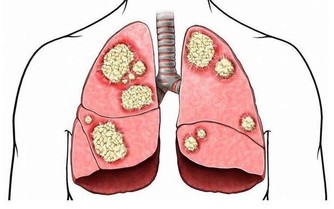

肝臟有不少“天敵”,首推肝炎病毒。換言之,肝炎病毒乃是肝臟健康的首要敵人,它們常將罹患者拖入肝炎——肝硬化——肝癌的死亡之路。目前科學家已發現甲、乙、丙、丁、戊、庚等6種型號肝炎病毒,其中尤以乙、丙、庚等型號最為凶險。最有效的手段是接種疫苗,如甲型、乙型肝炎疫苗。以甲型肝炎為例,疫苗應用近十年,受益者接近1億人,致使該型肝炎的感染率以每年平均22%的速度下降,估計20年後可消滅此病。

其次是藥物。調查資料顯示,藥物引起的肝損害約佔住院病人的10%。在老人組,這一發病率更高。據法國報導,在50歲以上的“急性肝炎”病人中,43%係由藥物所致。如阿司匹林、磺胺、青黴素、利福平等都是既常用又有害於肝的藥物。即使那些看似安全的藥物(如營養藥、補藥等),也可因誤用或濫用而給肝臟埋下隱患。故不要隨便用藥,尤其是口服藥,幾乎100%通過肝臟處理。即使是營養藥或補藥,也要接受醫生的指導,不可自作主張,以免增加肝臟的負擔。

再次是酒精。酒精是一種很奇特的分子,既能溶於水,又能溶於油,

一旦進入人體便如魚得水,無處不往,人體全身幾乎沒有它不能去的地方。

首先倒霉的便是肝臟,因為酒精本身就含有毒性,足以傷害肝臟,脂肪肝是最早出現的徵兆,

只需豪飲幾天便可以形成,接著導致“纖維化”,再變成酒精性肝病,隨後情況就更糟了,

最終發展到不可逆的“肝硬化”。